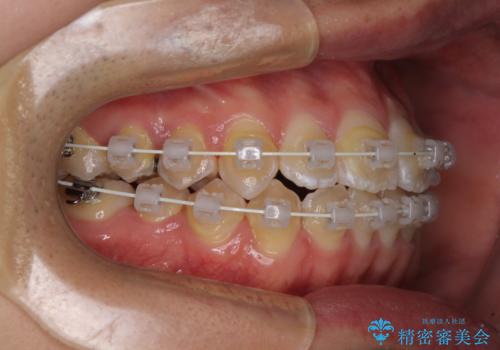

- 上下前歯のデコボコを気にして来院された患者様です。

ワイヤー矯正でもマウスピース矯正でも可能でしたが、短期間で、自身の手を煩わせることなく治療を行いたいとのことで、ワイヤー装置にて矯正治療を行うこととしました。

当初予定通り、1年間で治療を終えることができました。